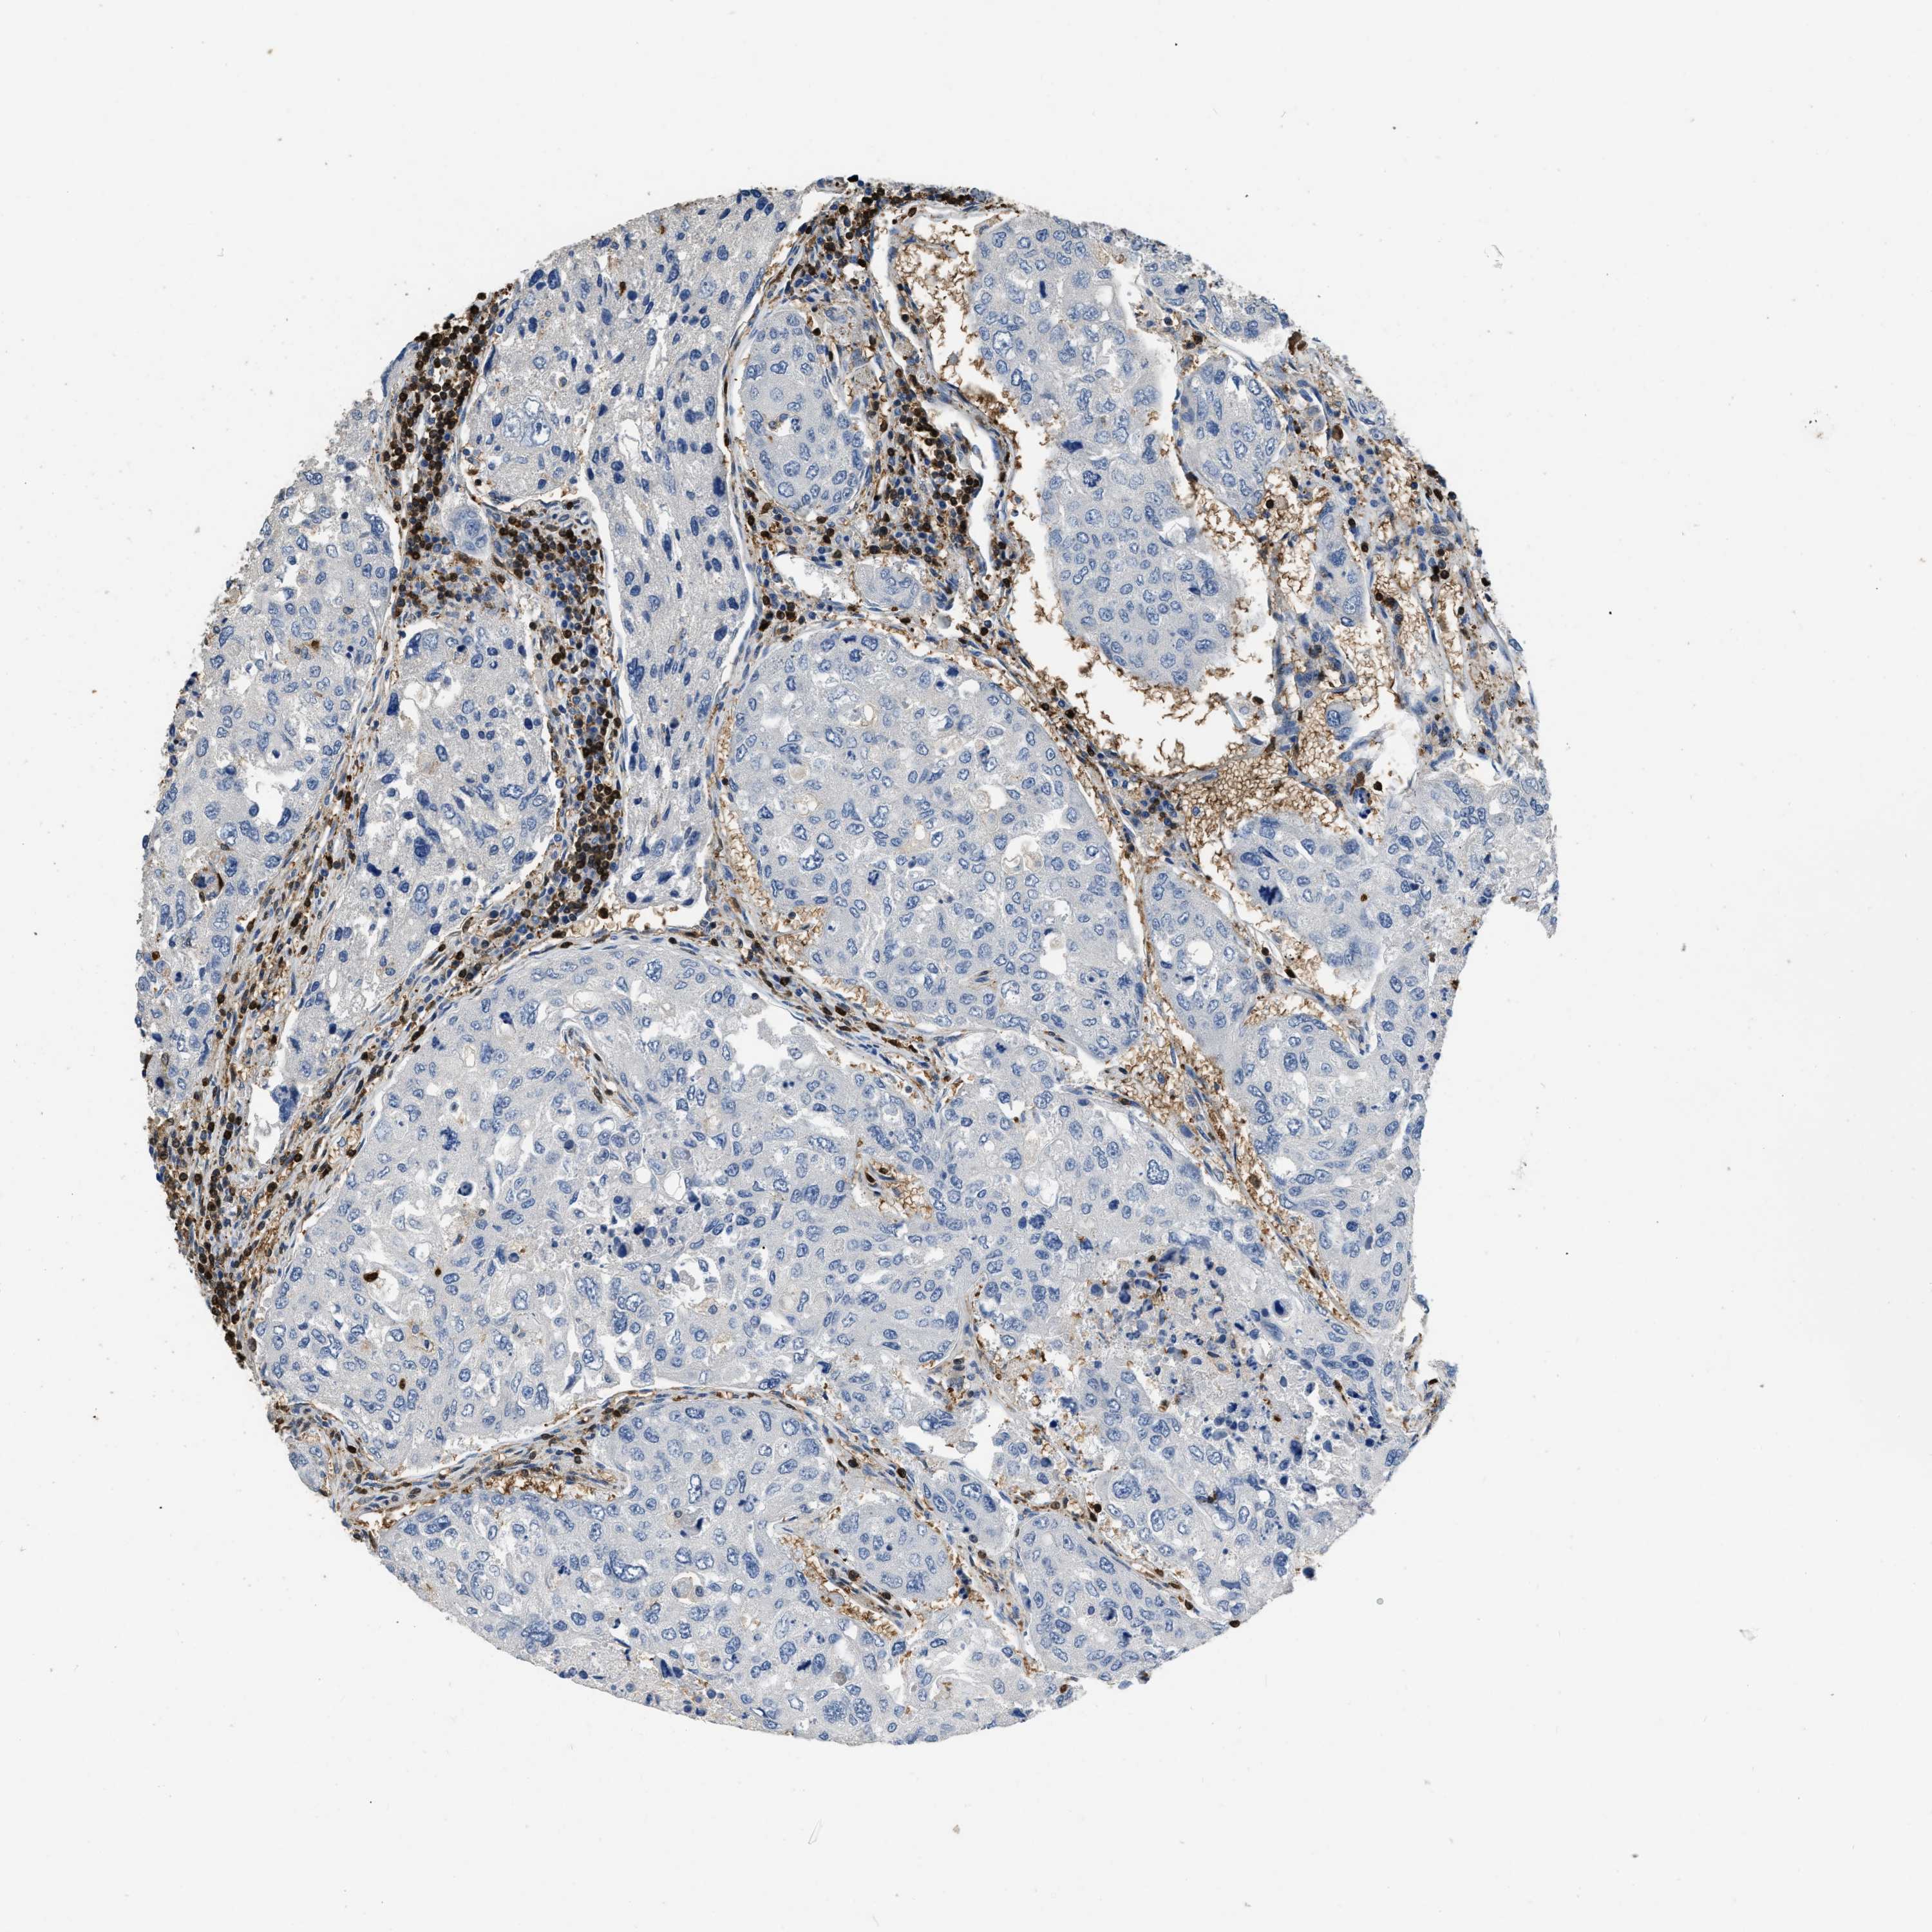

UROTHELIAL CANCER - Protein expressioni

A mouse-over function shows sample information and annotation data. Click on an image to view it in a full screen mode. Samples can be filtered based on level of antibody staining by selecting one or several of the following categories: high, medium, low and not detected. The assay and annotation is described here.

Note that samples used for immunohistochemistry by the Human Protein Atlas do not correspond to samples in the TCGA dataset.

Antibody stainingi

Antibody staining in the annotated cell types in the current human tissue is reported as not detected, low, medium, or high, based on conventional immunohistochemistry profiling in selected tissues. This score is based on the combination of the staining intensity and fraction of stained cells.

Each image is clickable and will lead to virtual microscopy that enables deeper exploration of all samples and also displays staining intensity scores, fraction scores and subcellular localization as well as patient and tissue information for each sample.

Antibody HPA051235

Antibody CAB018584

Staining

High

Medium

Low

Not detected

Intensity

Strong

Moderate

Weak

Negative

Quantity

>75%

75%-25%

<25%

None

Location

Nuclear

Cytoplasmic/membranous

Cytoplasmic/membranous,nuclear

Urothelial carcinoma, High grade

Urothelial carcinoma, NOS

Urothelial carcinoma, Low grade